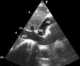

Cardiac tamponade, also known as pericardial tamponade, is when fluid in the pericardium (the sac around the heart) builds up, resulting in compression of the heart. Onset may be rapid or gradual. [Source: Wikipedia ]